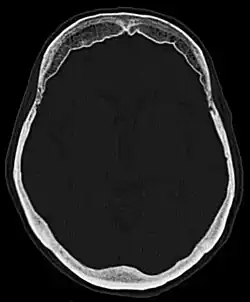

| Hyperostosis frontalis interna in a 74-year-old woman | |

Hyperostosis frontalis interna is a common, benign thickening of the inner side of the frontal bone of the skull. It is found predominantly in women after menopause and is usually asymptomatic. Mostly frequently it is found as an incidental finding discovered during an X-ray or CT scan of the skull.